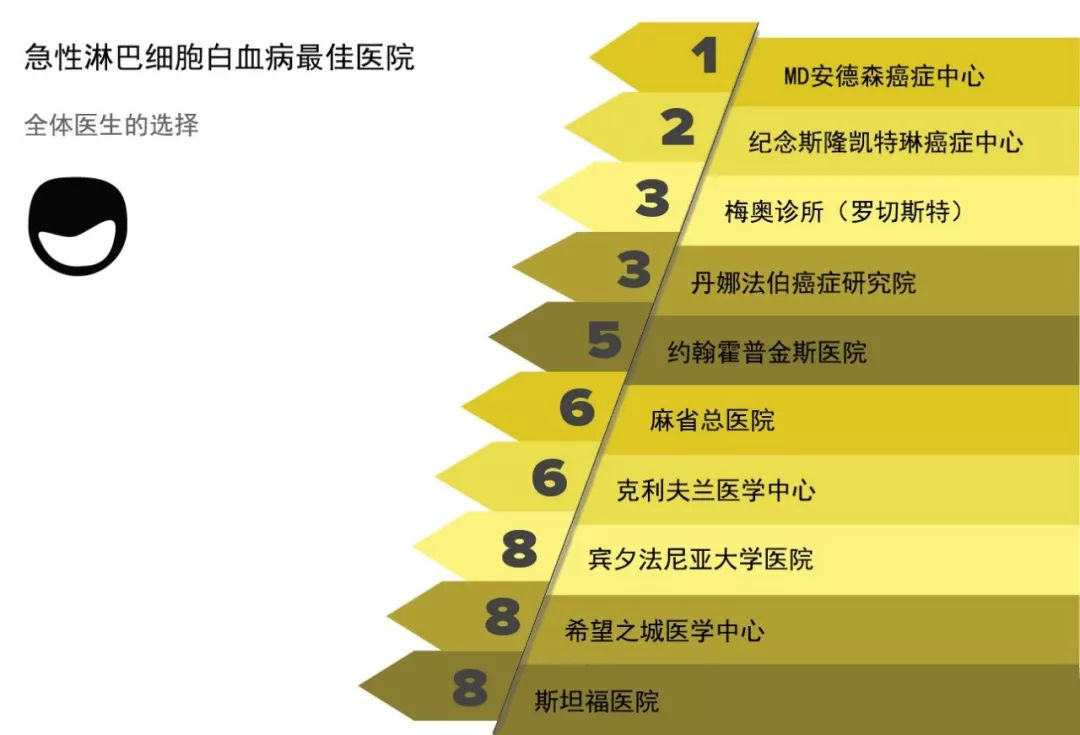

出国看病 美国医生眼中的医院 2018年新排名

出国看病 美国医生眼中的医院 2018年新排名